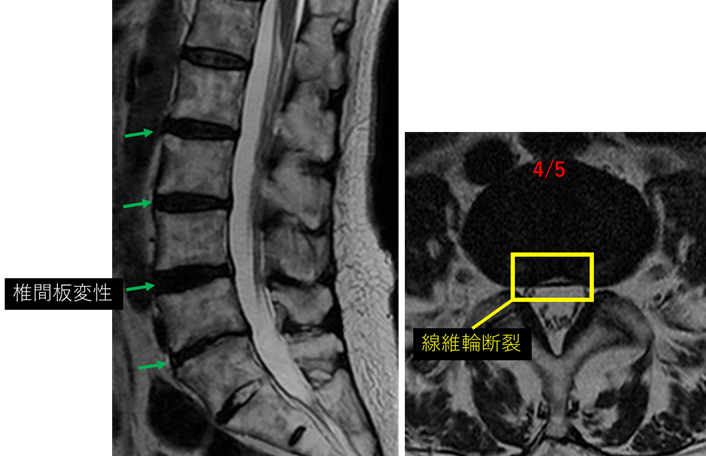

画像及び所見について

L2/3: 軽度椎間板変性

L3/4: 椎間板変性

L4/5: 椎間板変性、膨隆、繊維輪断裂

L5/S: 椎間板変性、膨隆

以上の事が画像上認められます。

L2/3、3/4、4/5、5/Sに

椎間板変性、膨隆、繊維輪断裂を認め、主症状の原因の可能性が高い。